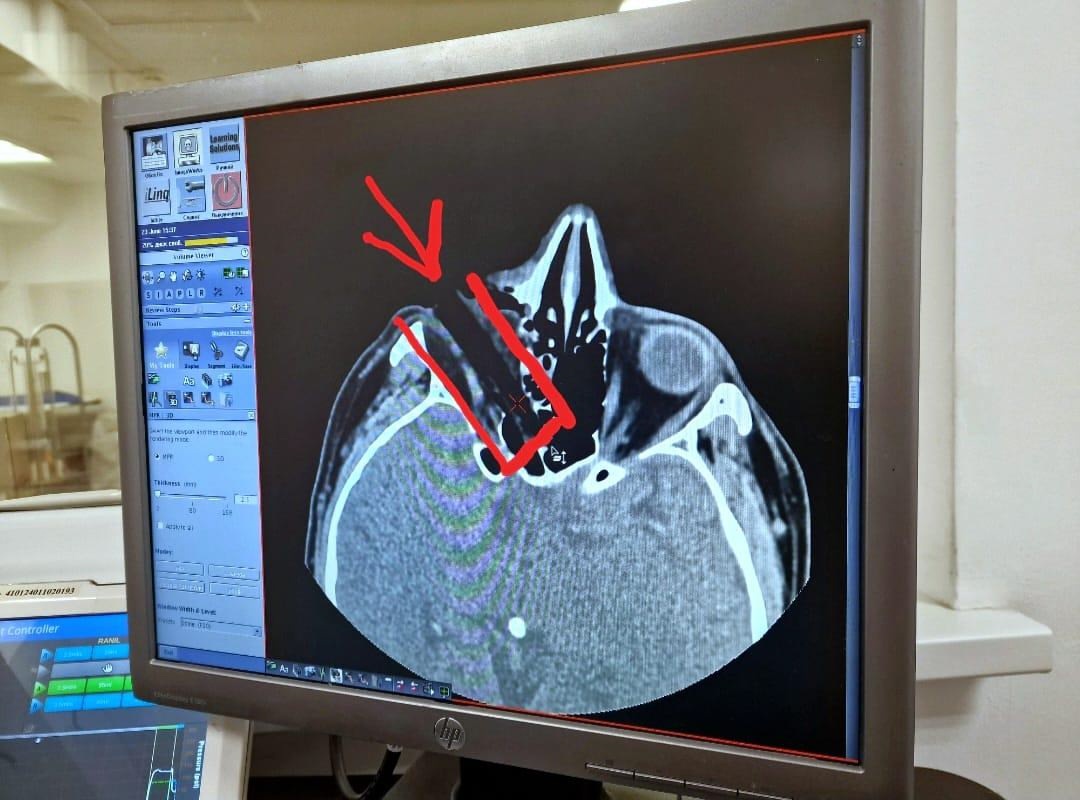

«Сучок вытолкнул глаз под череп и застрял в восьми миллиметрах от мозга», — поделились специалисты медучреждения, куда доставили мужчину.

Пациенту проводили сложнейшую операцию в течение часа. Сук достали. Затем удалили более 20 частиц коры и мелкого мусора. Зрение рыбаку удалось сохранить. Через несколько дней швы снимут. После челнинца выпишут из больницы.